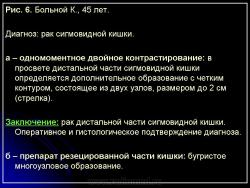

В 1961 г. Wellin предложил методику рентгенологического исследования толстой кишки, названную автором одномоментным двойным контрастированием толстой кишки (ОДКТК). Основное отличие ее от классической ирригоскопии состоит в том, что для исследования толстой кишки используется значительно меньшее количество бариевой взвеси и сразу же, по мере ее введения в дистальные отделы кишки, дальнейшее продвижение осуществляется специальным одноразовым устройством с помощью воздуха, вводимого под контролем рентгенотелевидения с учетом клинических особенностей пациента. Опыт многих исследователей и наш личный опыт указывают, что такие предосторожности при исследовании обусловлены не возможностью осложнений, а тем, что нередко быстрое контрастирование кишки может вызвать спазм отдельных ее участков и тем самым уменьшить его эффективность. Как правило, для исследования всех отделов толстой кишки, так же как и приирригоскопии, применяется стандартизованная методика с использованием тех же пяти проекций. Фиксация изображения осуществляется на рентгеновскую пленку средних размеров 18 х 24, 24 х 30 см. Основными достоинствами ОДКТК следует считать его высокую диагностическую эффективность, методическую простоту и возможность использования при скрининговых обследованиях групп риска по раку толстой кишки. В ОДКТК удачно сочетаются фазы “тугого” наполнения и двойного контрастирования – основные элементы, позволяющие фиксировать внутристеночную инфильтрацию кишки в ее начальных проявлениях с помощью определения состояния контура кишки и толщины стенки. Двойное контрастирование позволяет получить исчерпывающую информацию о слизистой кишки, которая при отсутствии в ней изменений (небольших полиповидных образований, изъязвлений и др.) должна быть полностью разглажена и лишена складчатости (рис. 1).

В 1961 г. Wellin предложил методику рентгенологического исследования толстой кишки, названную автором одномоментным двойным контрастированием толстой кишки (ОДКТК). Основное отличие ее от классической ирригоскопии состоит в том, что для исследования толстой кишки используется значительно меньшее количество бариевой взвеси и сразу же, по мере ее введения в дистальные отделы кишки, дальнейшее продвижение осуществляется специальным одноразовым устройством с помощью воздуха, вводимого под контролем рентгенотелевидения с учетом клинических особенностей пациента. Опыт многих исследователей и наш личный опыт указывают, что такие предосторожности при исследовании обусловлены не возможностью осложнений, а тем, что нередко быстрое контрастирование кишки может вызвать спазм отдельных ее участков и тем самым уменьшить его эффективность. Как правило, для исследования всех отделов толстой кишки, так же как и приирригоскопии, применяется стандартизованная методика с использованием тех же пяти проекций. Фиксация изображения осуществляется на рентгеновскую пленку средних размеров 18 х 24, 24 х 30 см. Основными достоинствами ОДКТК следует считать его высокую диагностическую эффективность, методическую простоту и возможность использования при скрининговых обследованиях групп риска по раку толстой кишки. В ОДКТК удачно сочетаются фазы “тугого” наполнения и двойного контрастирования – основные элементы, позволяющие фиксировать внутристеночную инфильтрацию кишки в ее начальных проявлениях с помощью определения состояния контура кишки и толщины стенки. Двойное контрастирование позволяет получить исчерпывающую информацию о слизистой кишки, которая при отсутствии в ней изменений (небольших полиповидных образований, изъязвлений и др.) должна быть полностью разглажена и лишена складчатости (рис. 1).

В 1961 г. Wellin предложил методику рентгенологического исследования толстой кишки, названную автором одномоментным двойным контрастированием толстой кишки (ОДКТК). Основное отличие ее от классической ирригоскопии состоит в том, что для исследования толстой кишки используется значительно меньшее количество бариевой взвеси и сразу же, по мере ее введения в дистальные отделы кишки, дальнейшее продвижение осуществляется специальным одноразовым устройством с помощью воздуха, вводимого под контролем рентгенотелевидения с учетом клинических особенностей пациента. Опыт многих исследователей и наш личный опыт указывают, что такие предосторожности при исследовании обусловлены не возможностью осложнений, а тем, что нередко быстрое контрастирование кишки может вызвать спазм отдельных ее участков и тем самым уменьшить его эффективность. Как правило, для исследования всех отделов толстой кишки, так же как и приирригоскопии, применяется стандартизованная методика с использованием тех же пяти проекций. Фиксация изображения осуществляется на рентгеновскую пленку средних размеров 18 х 24, 24 х 30 см. Основными достоинствами ОДКТК следует считать его высокую диагностическую эффективность, методическую простоту и возможность использования при скрининговых обследованиях групп риска по раку толстой кишки. В ОДКТК удачно сочетаются фазы “тугого” наполнения и двойного контрастирования – основные элементы, позволяющие фиксировать внутристеночную инфильтрацию кишки в ее начальных проявлениях с помощью определения состояния контура кишки и толщины стенки. Двойное контрастирование позволяет получить исчерпывающую информацию о слизистой кишки, которая при отсутствии в ней изменений (небольших полиповидных образований, изъязвлений и др.) должна быть полностью разглажена и лишена складчатости (рис. 1).